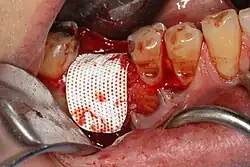

Socket preservation attempts to prevent bone loss by bone grafting the socket immediately after extraction. With the procedure, the gum is retracted, the tooth is removed, material (usually a bone substitute) is placed in the tooth socket, it is covered with a barrier membrane, and sutured closed.[2] Roughly 30 days after socket preservation, the barrier membrane is either removed, or it resorbs, and the callous of bone covers with new gingiva. While there is good evidence that socket preservation prevents bone loss, there is no definitive proof that this leads to higher implants success or long-term health.[4]

Socket preservation is completed at the time of extraction. After removal of the tooth, the gum is elevated away from the bone, the socket is thoroughly cleansed, and antibiotic powder may be used. A barrier membrane is then fastened to the gum, the socket is packed with bone grafting material and the wound closed over the barrier membrane. Where the barrier membrane does not dissolve, it is removed approximately 30 days after placement,[5] and the graft becomes incorporated into the healing bone 3–9 months later.

Barrier membranes can be either resorbable, or non-resorbable. The standard non-resorbable membrane is expanded polytetrafluoroethylene (ePTFE) which was first used in 1984, when it was found to be biocompatible. There are a variety of resorbable membranes, including collagen,[7] and synthetic resorbable (lactic acid or glycolic acid).